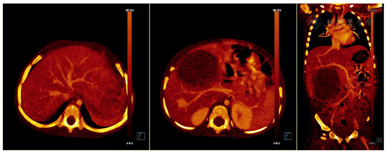

CT图像显示肝右前叶见一巨大囊实性肿物,大小约83mm×63mm×99mm,肿物以囊性成分为主,见粗细不均匀分隔,实性成分呈结节状、斑片状向囊腔内突出,增强后分隔及实性成分见轻度强化,肿物内见纤细血管影,肿块下方部分向腹腔内突出,边界清楚,内壁光滑(图1和图2)。患者随后行"剖腹探查,肝癌切除,胆囊切除,门静脉探查术",冰冻病理示:形态较符合间叶性错构瘤。石蜡切片示肝组织内可见大量疏松水肿的纤维结缔组织明显增生伴粘液样变,其内见萎缩的肝细胞岛,形态符合肝间叶性错构瘤。

DECT采用选择性光子屏蔽(SPS Ⅱ)技术,在70kV和150kV的电压组合下实现能谱的显著分离。使用syngo.CT DE Virtual Unenhanced生成碘图/VNC融合图像,能显著提高血管和肿瘤的观察能力(图1和图2)。虚拟non-contrast(VNC)图像与常规平扫图像一致性匹配(图3),VNC可取代平扫,减少扫描次数做到降低总的剂量,提高合规管理和安全的儿童CT扫描使用。使用syngo.CT DE Monoenergy Plus,在这两个kV设置下获得的衰减值用于显示不同keV水平的图像。与在120kV下采集的常规CT图像相比,低keV的图像对比度显著增强,使得肿瘤侵犯的范围显示更加清晰(图4),低keV图像对比度是非常优异的(图5)。DECT的优势在于搭配西门子CT独有的水冷球管系统,双能力模式中两套球管独立工作,在同一辐射剂量的水平下,在不影响扫描流程和在不增加设备损耗的前提下,实现常规剂量成像,图像质量优异。70/Sn150kV的电压组合是目前用于儿童能量成像的最优参数设置。为了实现儿童低剂量能量检查,其他先进的技术也被使用,如CARE Dose 4D(实时自动曝光控制)和ADMIRE(高级模型迭代重建)。在本病例中,儿童多期CT检查,其中平扫、动脉期和静脉期用双能量技术,延迟期用自由呼吸大螺距技术,多期联扫总的辐射剂量仅为2.85mSv,为传统CT检查的2/5。